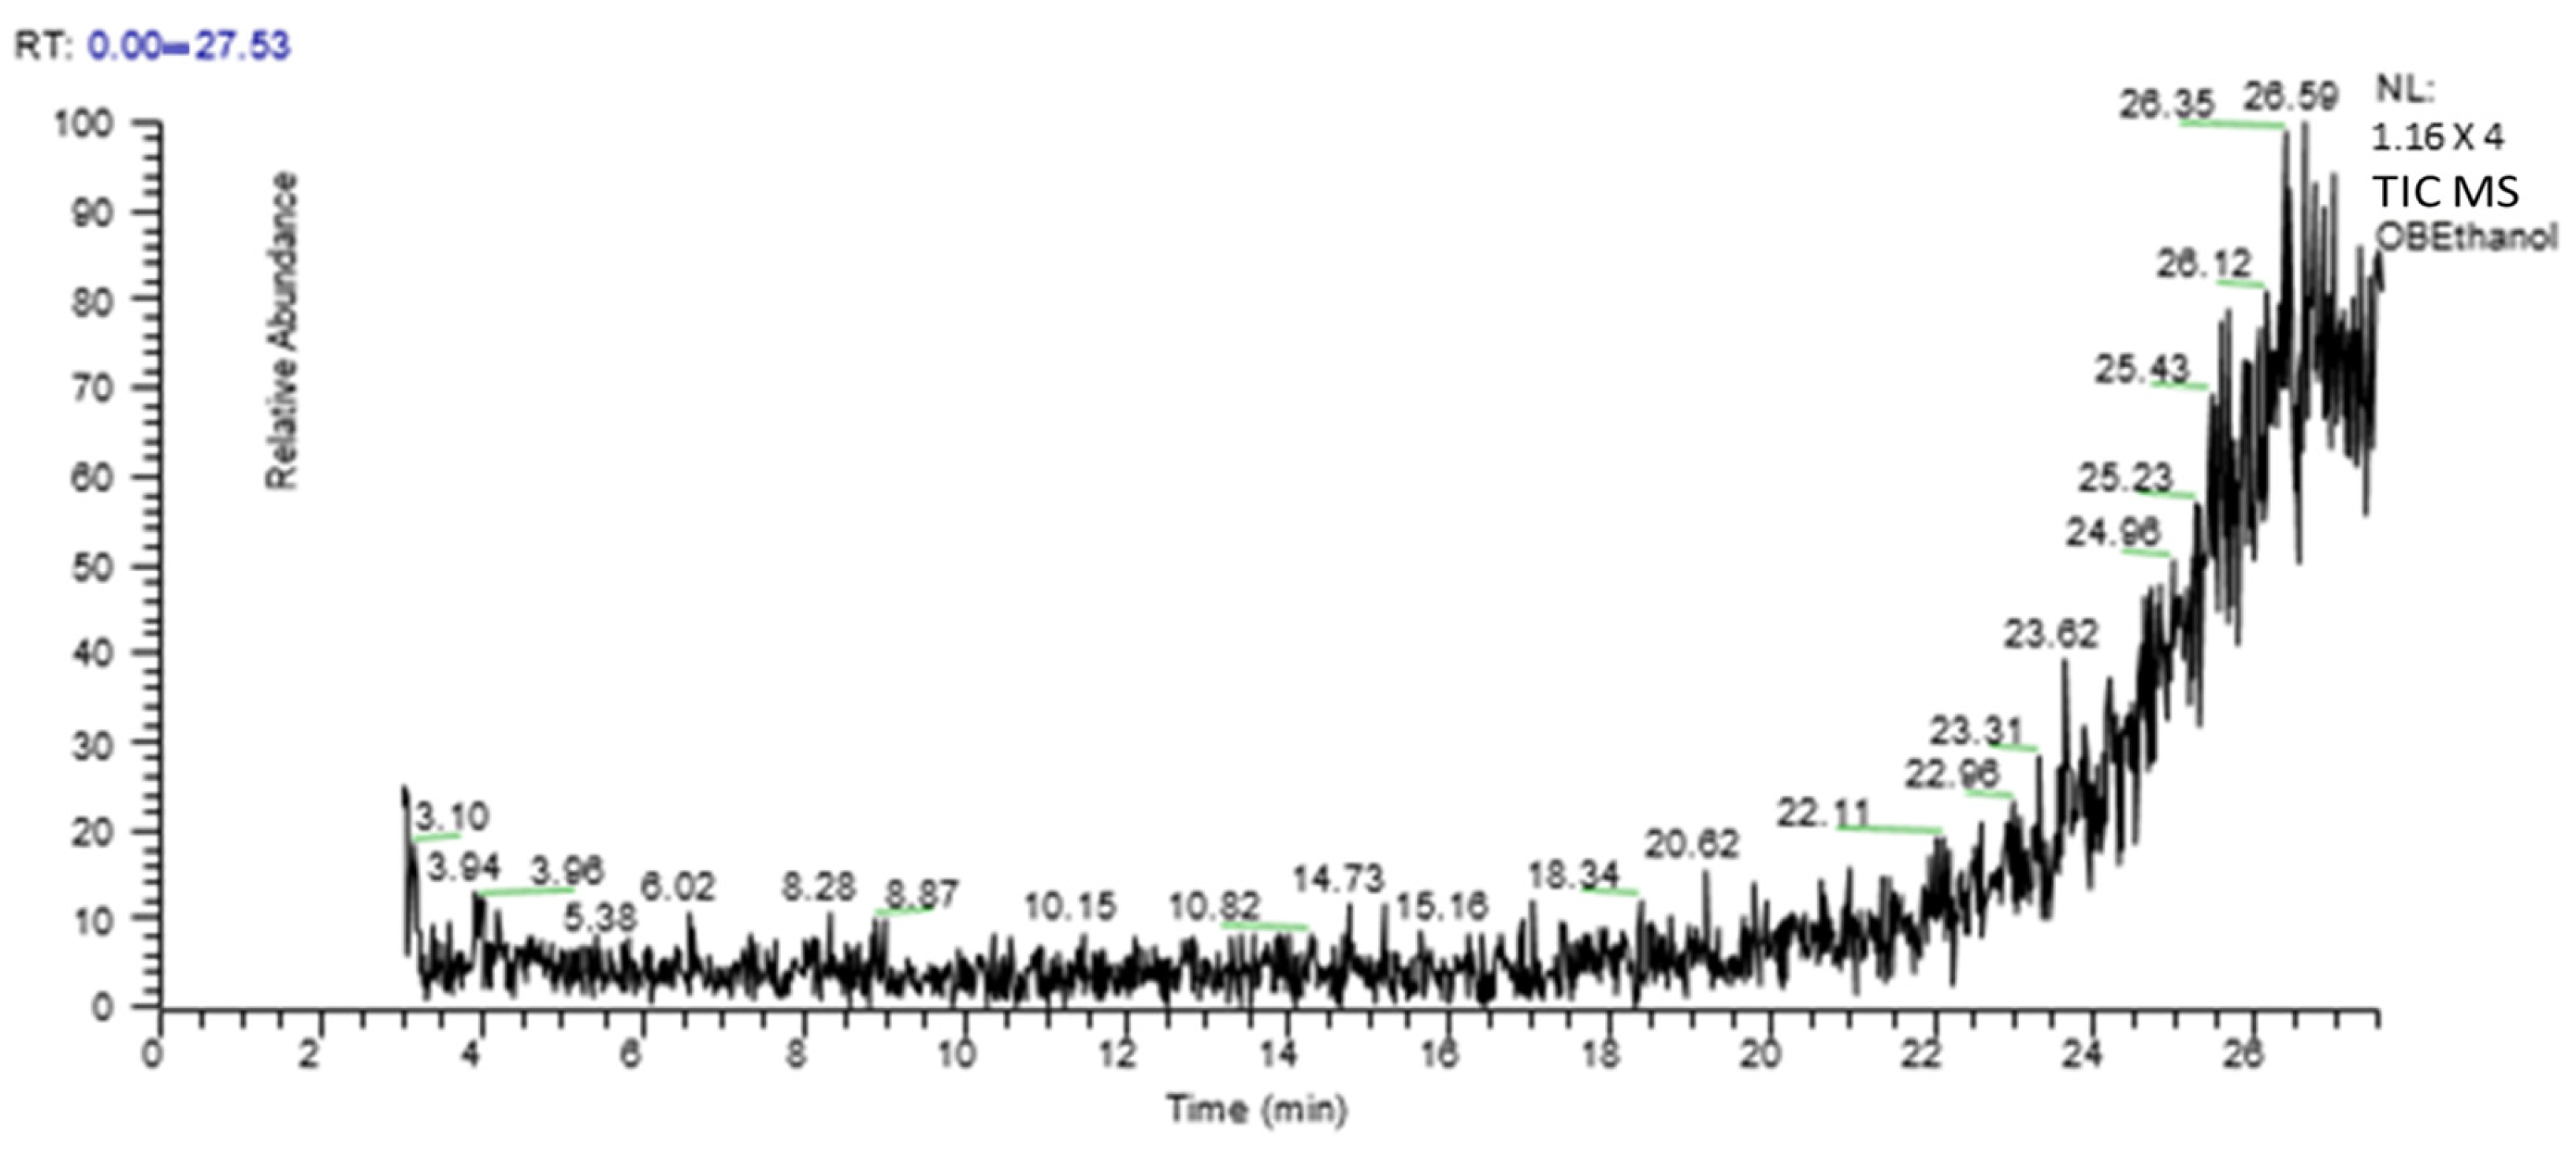

2.3. Gas Chromatography–Mass Spectrometry (GC-MS) Analysis

4.5. Estimation of Gas Chromatography–Mass Spectrometry (GC-MC)

| S. No. | Compound | M.W | Formula | Class | RT | Area % | Biological Activities | Ref. |

|---|---|---|---|---|---|---|---|---|

| 1. | Matrine | 248 | C15H24N2O | Alkaloid | 3.94 | 3.09 | Antitumor, anti-inflammatory | [15,16] |

| 2. | 3′,4′,5,7-Tetramethoxyflavone | 342 | C19H18 O6 | Flavonoid | 6.02 | 0.29 | Antioxidant | [17] |

| 3. | 6-ethyl-2,3,5,7-tetrahydroxy, 1,4-Naphthoquinone | 250 | C12H10O6 | Spinochrome | 10.15 | 0.92 | Anti-inflammatory, Antimicrobial | [18] |

| 4. | Thebaine | 311 | C19H21NO3 | Opiate alkaloid | 10.82 | 0.64 | Analgesic | [19] |

| 5. | Pyrrolidine | 207 | C14H25N | Alkaloid | 15.16 | 0.57 | Anticancer, anti-inflammatory, antiviral, anti-tuberculosis | [20] |

| 6. | Quercetin-4’-glucoside | 464 | C21H20O12 | Flavonoid o-glycosides | 15.65 | 0.54 | Antioxidant, anti-inflammatory | [21] |

| 7. | Cyclohexane, 1,1′-(2-methyl-1,3 propanediyl) bis- | 222 | C16H30 | - | 20.62 | 1.07 | Antioxidant | [22] |

| 8. | 2,4,6-Cycloheptatrien-1-one,3,5-bis-trimethylsilyl- | 250 | C13H22OSi2 | - | 26.65 | 16.73 | Antioxidant, antimicrobial | [23] |